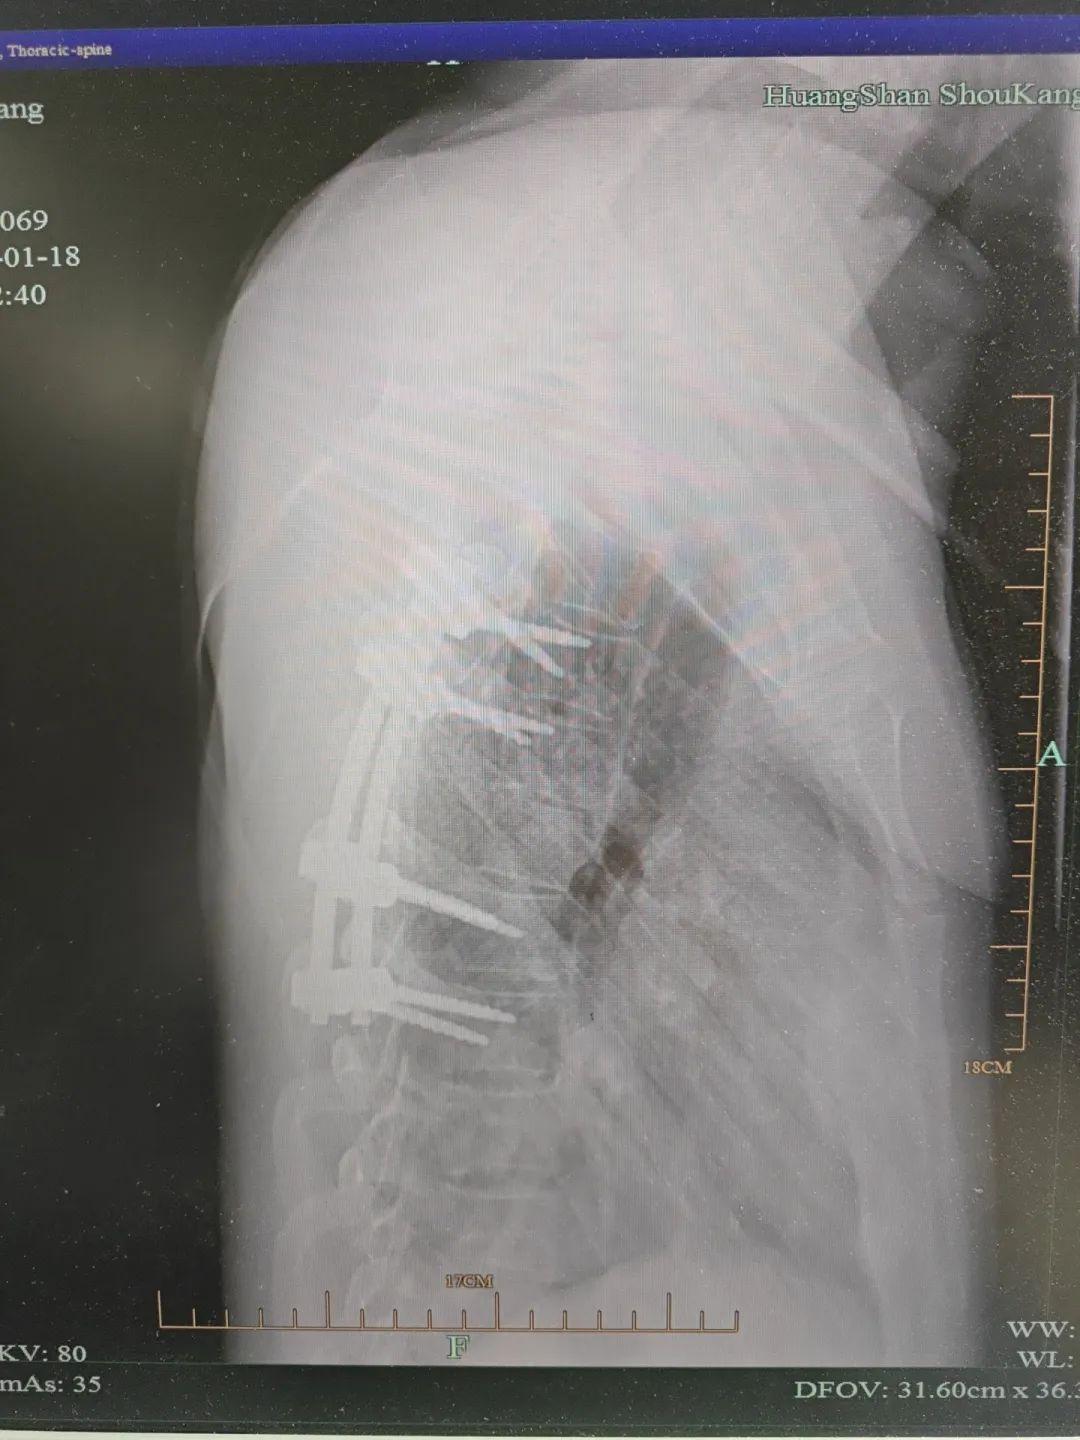

▲术后摄片示内固定在位,脊柱稳定性得到重建